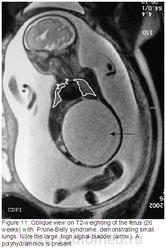

Рисунок 1: